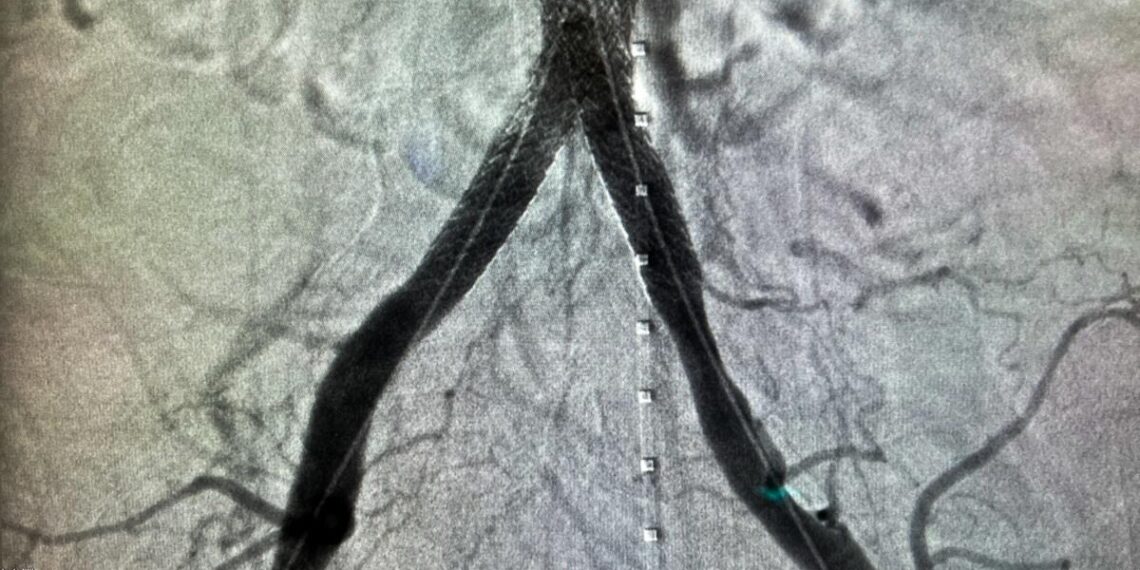

La Spitalul Clinic Județean de Urgență „Pius Brînzeu” din Timișoara a fost realizată cu succes prima intervenție de acest tip din cadrul instituției – un tratament endovascular minim invaziv pentru ocluzia completă a aortei abdominale, utilizând tehnica modernă CERAB.

Intervenția a fost realizată de către Dr. Morelli Marialuisa, medic specialist în chirurgie vasculară și endovasculară, marcând o premieră în tratamentul ocluziilor aorto-iliace complexe prin abord endovascular.

Tehnica CERAB oferă o alternativă eficientă și sigură la chirurgia deschisă, reducând semnificativ riscurile perioperatorii, pierderile sangvine, durata intervenției și timpul de recuperare postoperatorie, în timp ce asigură o reconstrucție fiziologică a bifurcației aortice.